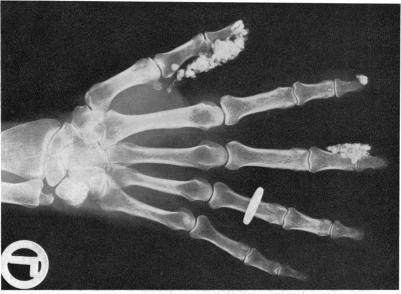

The heart in scleroderma.

Br Heart J. 1961 May;23(3):243-59. doi: 10.1136/hrt.23.3.243.

https://cdn.ncbi.nlm.nih.gov/pmc/blobs/d679/1017763/d4e5d377c1b7/brheartj00362-0031-a.jpg